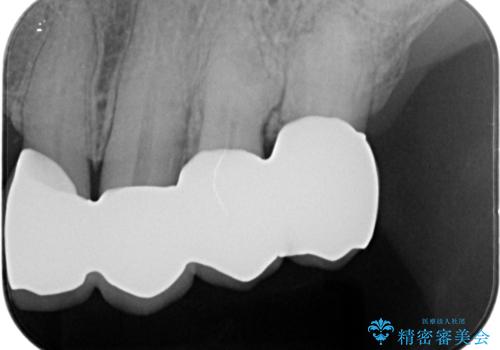

咬合の崩壊 金属床義歯で咬合機能の回復

「大規模な手術は避けたい。」と言う希望を鑑み、インプラントではなく残せる歯の連結セラミッククラウンの作製、金属床義歯を用いてしっかりと咬合機能を回復できるよう治療を進めます。

- 110万円(ジルコニアクラウン×7・仮歯×7 金属床義歯)費用は治療当時の料金となります

年齢と体調を考慮して、インプラントではなく入れ歯で咬合機能の回復を達成する治療計画としました。